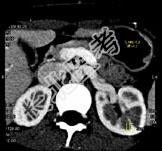

- 多项选择题女,24岁, 发作性肉眼血尿1年,实验室检查: 尿蛋白(-~+)、红细胞(1~2/HP),尿蛋白直立试验(+), CT扫描如图,下列说法正确的是 ( )

A、双肾大小形态正常

B、左肾静脉走行至肠系膜上动脉与腹主动脉间变细,近左肾处扩张

E、考虑为左肾静脉胡桃夹综合征